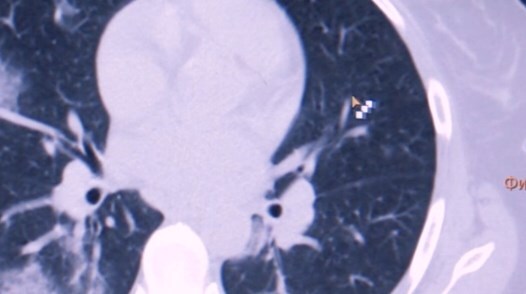

Японские и американские врачи обнаружили патологию у людей, которые переболели коронавирусом без симптомов.

У некоторых пациентов происходят изменения в легких.

Отмечается, что человек чувствует себя нормально, но коронавирус повреждает легочную ткань, на которой образуются уплотнения.